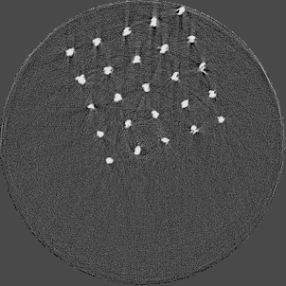

Figure 5 illustrates a single slice spectral reconstruction of the Ti scaffold. Varying levels of streak artefacts can be seen across the spectral reconstructions. The spectral reconstructions for the energy ranges 35 to 80 keV, 55 to 80 keV, and 62 to 80 keV shown in figure 5, exhibit reduced streak artefacts. A region-of-interest (ROI) analysis was performed in the immediate vicinity of the metal region where the streaks are more pronounced. Average attenuation coefficent of air close to zero conveys less regional noise/artefacts. The regional average attenuation coefficient (μROIsubscript𝜇𝑅𝑂𝐼\mu_{ROI}) of the non-metal (air) region in 55 to 80 keV reconstruction (figure 5c) shows reduced artefacts. Even though minor streaks and statistical noise appear in figure 5d due to photon limitation, the artefacts are less pronounced in comparison to the wide energy acquisition in figure 5a.

Refer to caption

(a) 15 to 80 keV

(b) 35 to 80 keV

(c) 55 to 80 keV

(d) 62 to 80 keV

Figure 5: Single slice spectral reconstruction of Ti scaffold sample. μROIsubscript𝜇𝑅𝑂𝐼\mu_{ROI} is 0.246, 0.030, 0.008 and 0.103 for the circular ROI in (a), (b), (c) and (d) respectively.